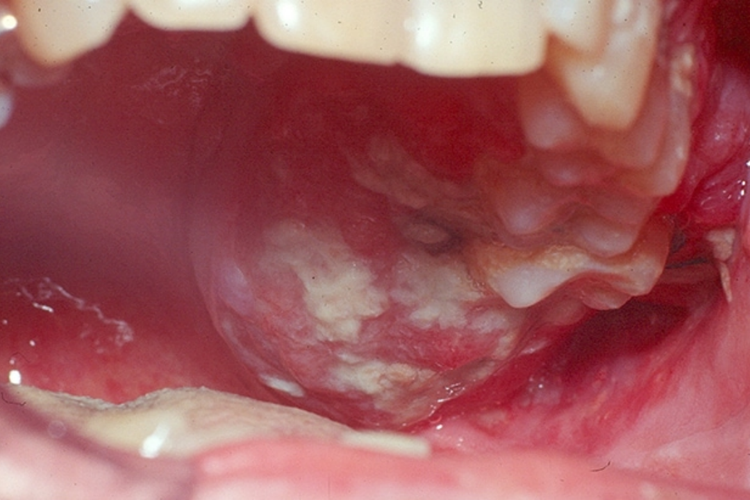

颊癌:由白斑发展而来的颊癌,常可在患区查见白斑。早期一般无明显疼痛,当癌肿浸润肌肉等深层组织或合并感染时,出现明显疼痛,伴不同程度的张口受限,直至牙关紧闭。牙周组织受累后,可出现牙痛或牙松动。由于癌瘤浸润、溃疡形成,特别是伴发感染时,可引起局部继发性出血,疼痛加重。患者常有下颌下淋巴结肿大,亦可累及颈深上淋巴结群。